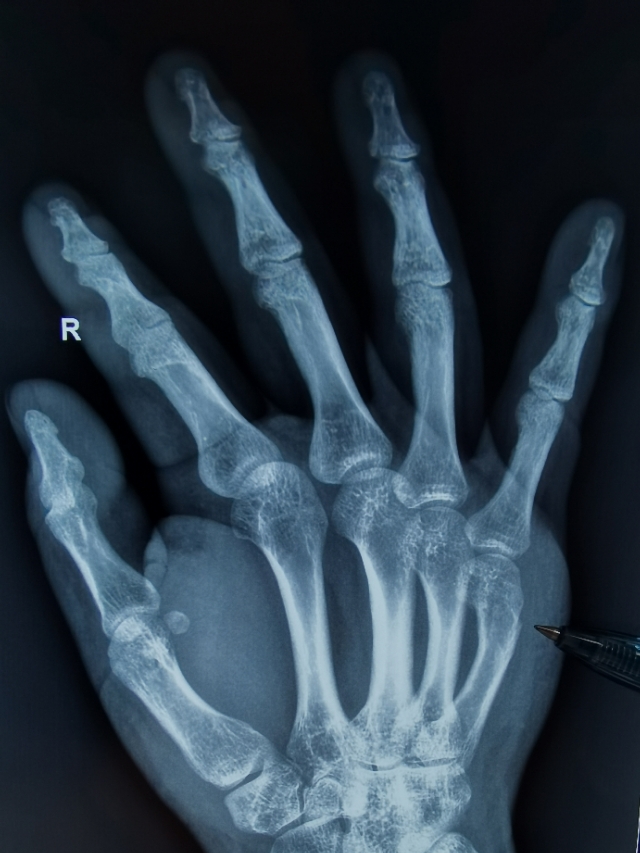

手的第五掌骨颈骨折又称“拳击骨折”,多见于拳头猛然击人、击物、打墙等时损伤。骨折多呈横断或粉碎性,但横断更多见。骨折后由于手部小肌肉的牵拉,掌骨头向掌侧倾斜,骨折向背侧成角。X线片检查可以明确诊断。

固定后常规需拍摄X线片,检查整复位置是否理想,以后每周复诊换药1-2次,一般需限制活动4~6周即可痊愈。